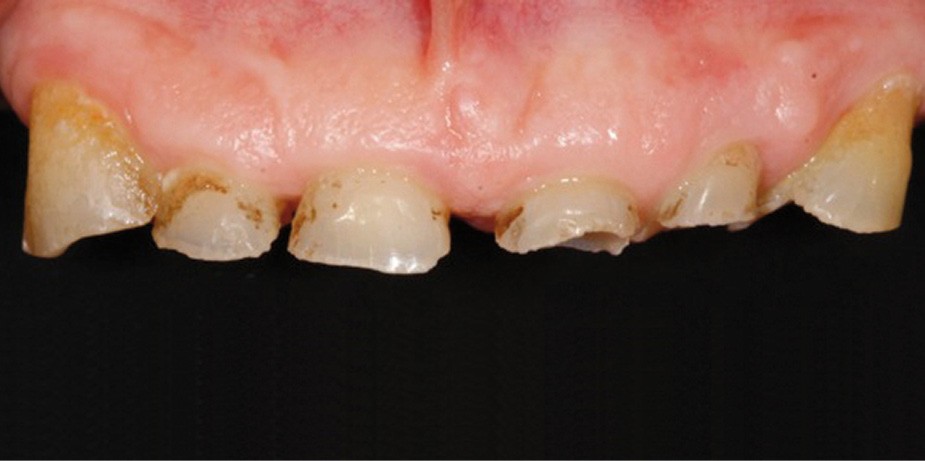

• Le bilan esthétique nous indique plusieurs points disgracieux :

– dysharmonie des contours gingivaux (ligne des collets) avec une ligne du sourire basse [1] ;

– perte de substance extrême du bloc incisivo-canin maxillaire et des incisives mandibulaires ;

– visibilité très limitée des dents lors d’un sourire forcé ;

– égressions compensatoires.